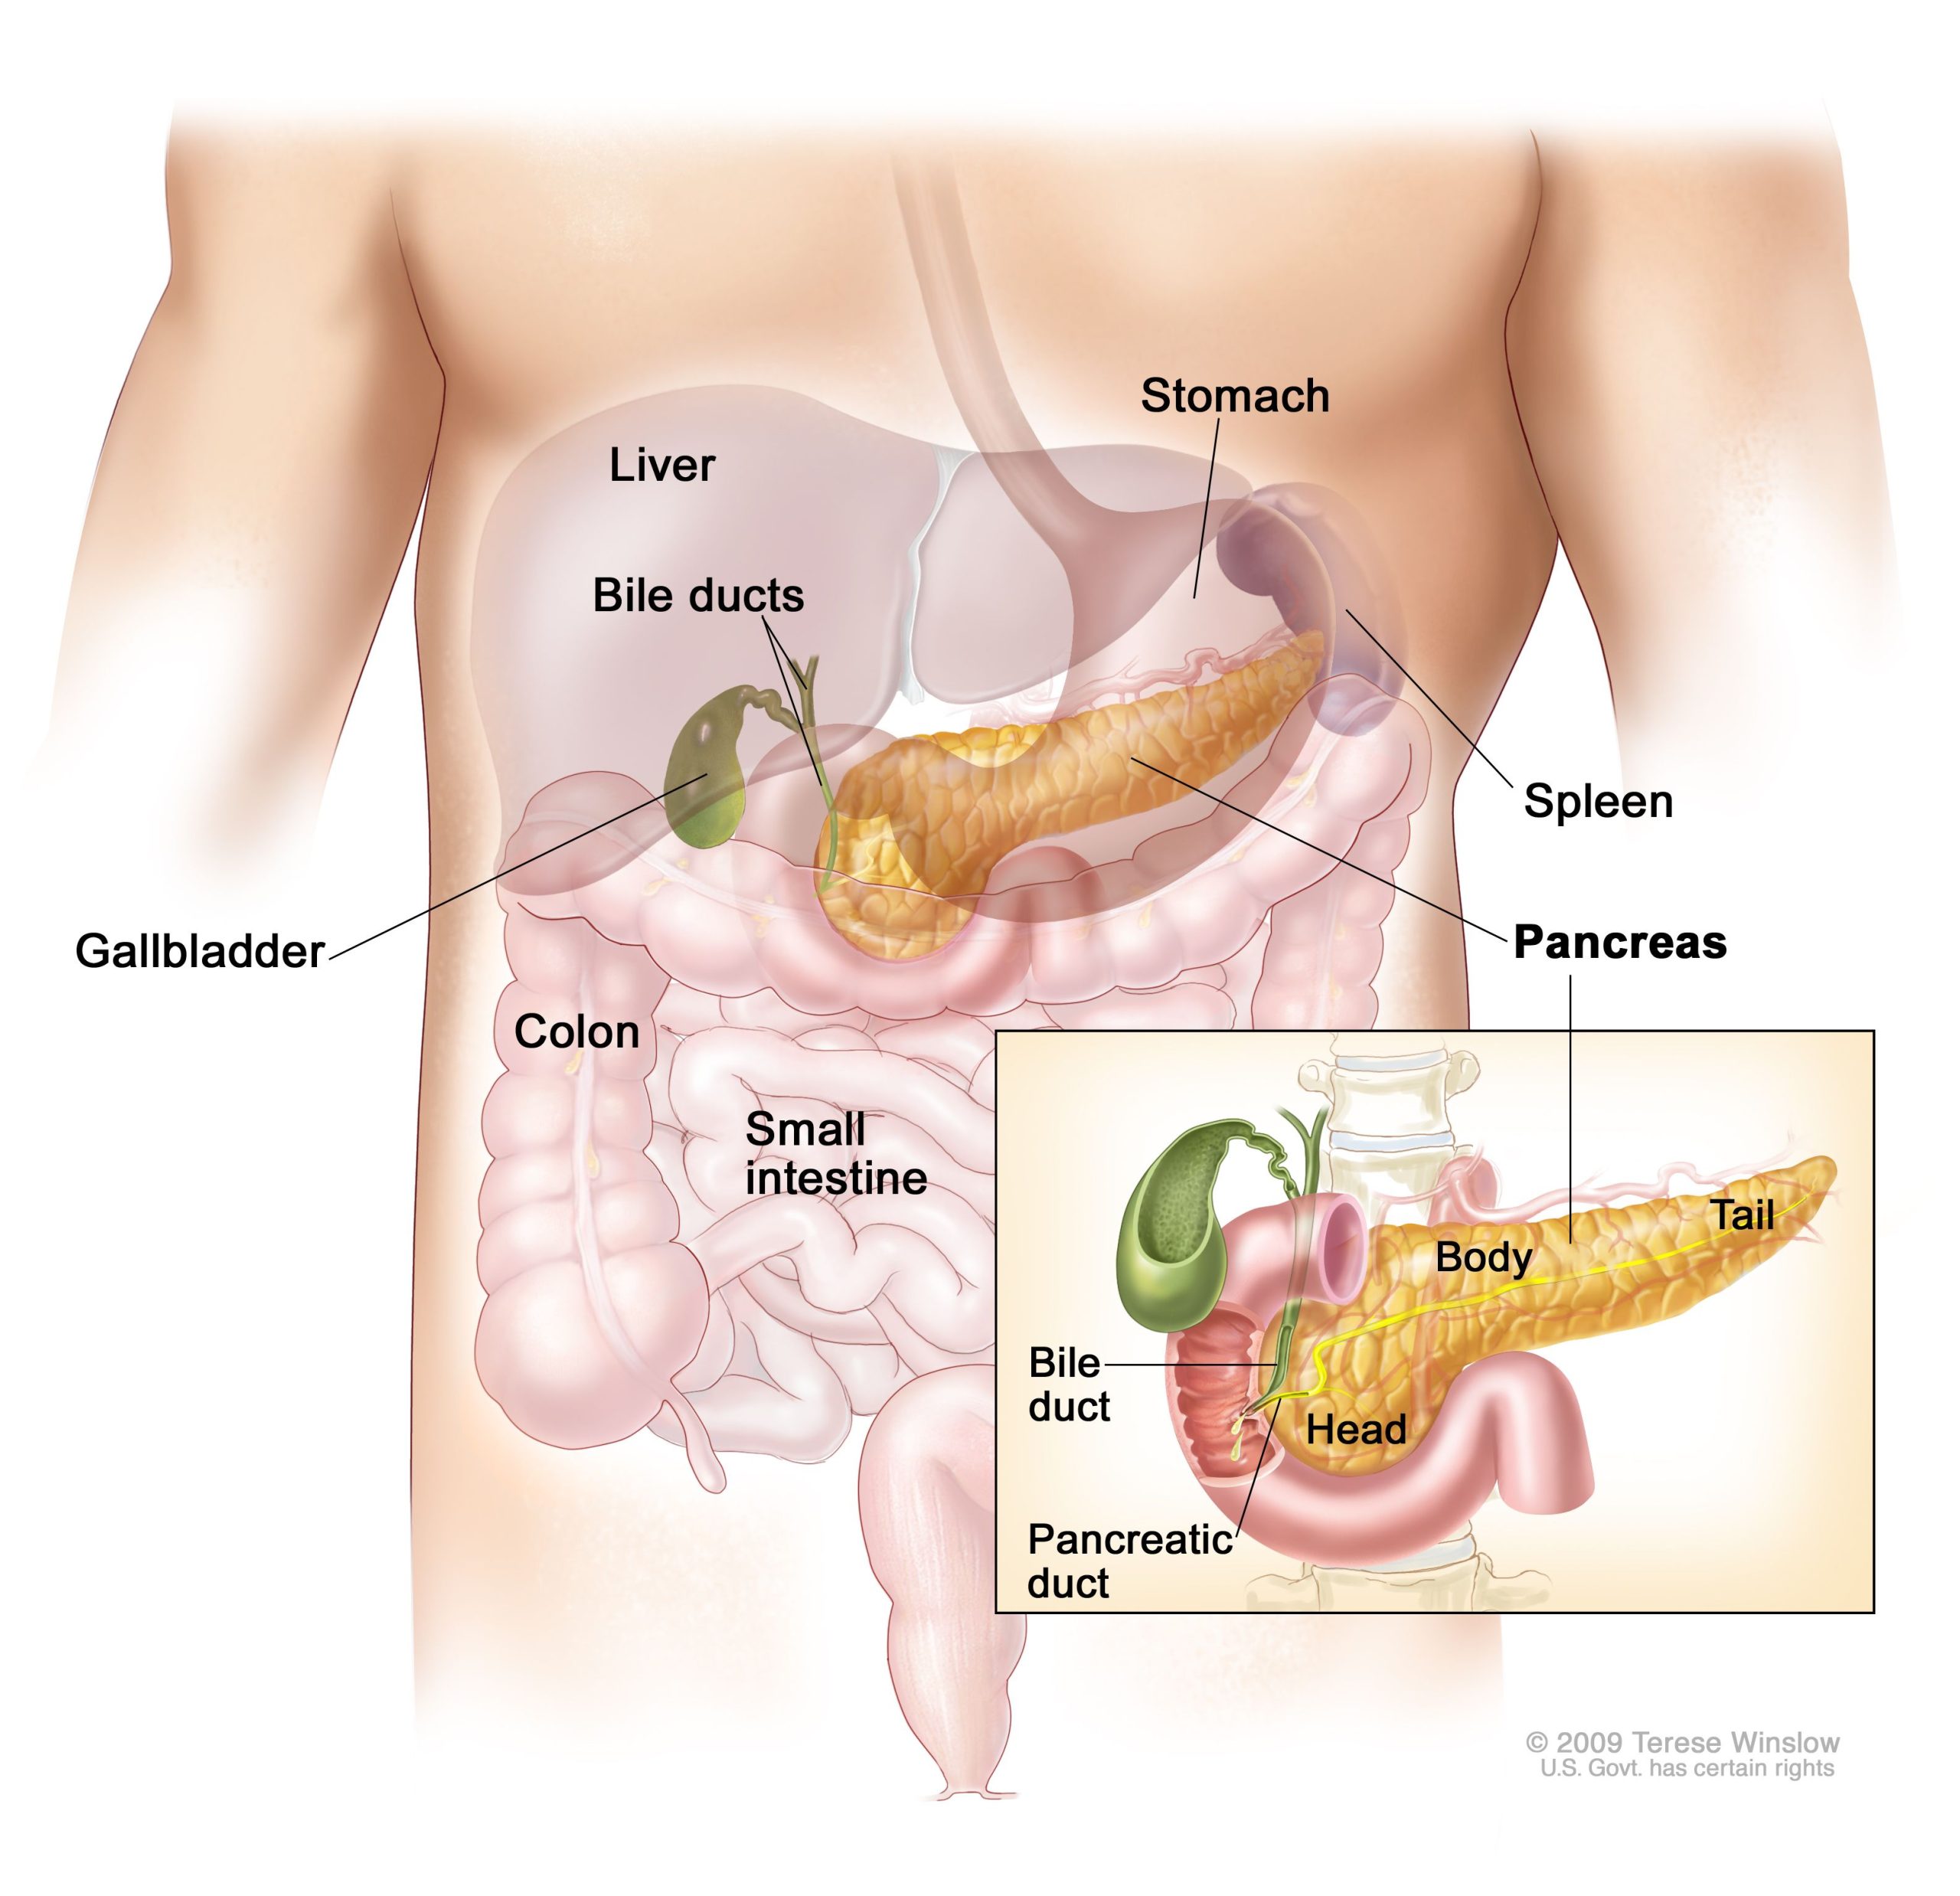

Pancreatic cancer begins in the tissues of your pancreas — an organ in your abdomen that lies behind the lower part of your stomach. Your pancreas releases enzymes that aid digestion and produces hormones that help manage your blood sugar.